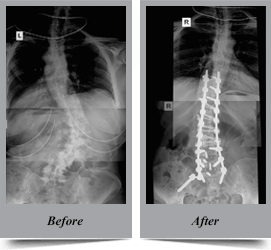

Congenital Scoliosis

Congenital scoliosis is the lateral curvature of spine that occurs in children